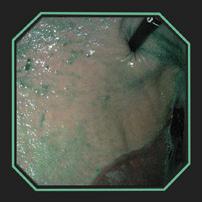

VISUALIZING SLIMER AT WORK

DISTRIBUTION OF SLIMER THROUGHOUT SQUAMOUS AND GLANDULAR REGIONS

DISTRIBUTION OF SLIMER (without color dye) SHOWING PRODUCT GRANULARITY

The above gastroscopy images show Slimer coating the stomach. The horses received 2oz of Slimer via syringe and then lunged at the walk and trot for 10-15 minutes to simulate splashing acid while being ridden. Though Slimer is brown, it was initially dyed blue to be more visible. In order to show that the blue dye did not discolor the stomach or disassociate from Slimer, over 90cc of water was inserted through the gastroscope to “rinse” a portion showing that the underlying tissue remained pink.

DEMARCATION AREA RINSED WITH WATER HIGHLIGHTING SLIMER’S GRANULARITY

DISTRIBUTION OF SLIMER (without color dye) THROUGHOUT SQUAMOUS AND GLANDULAR REGIONS